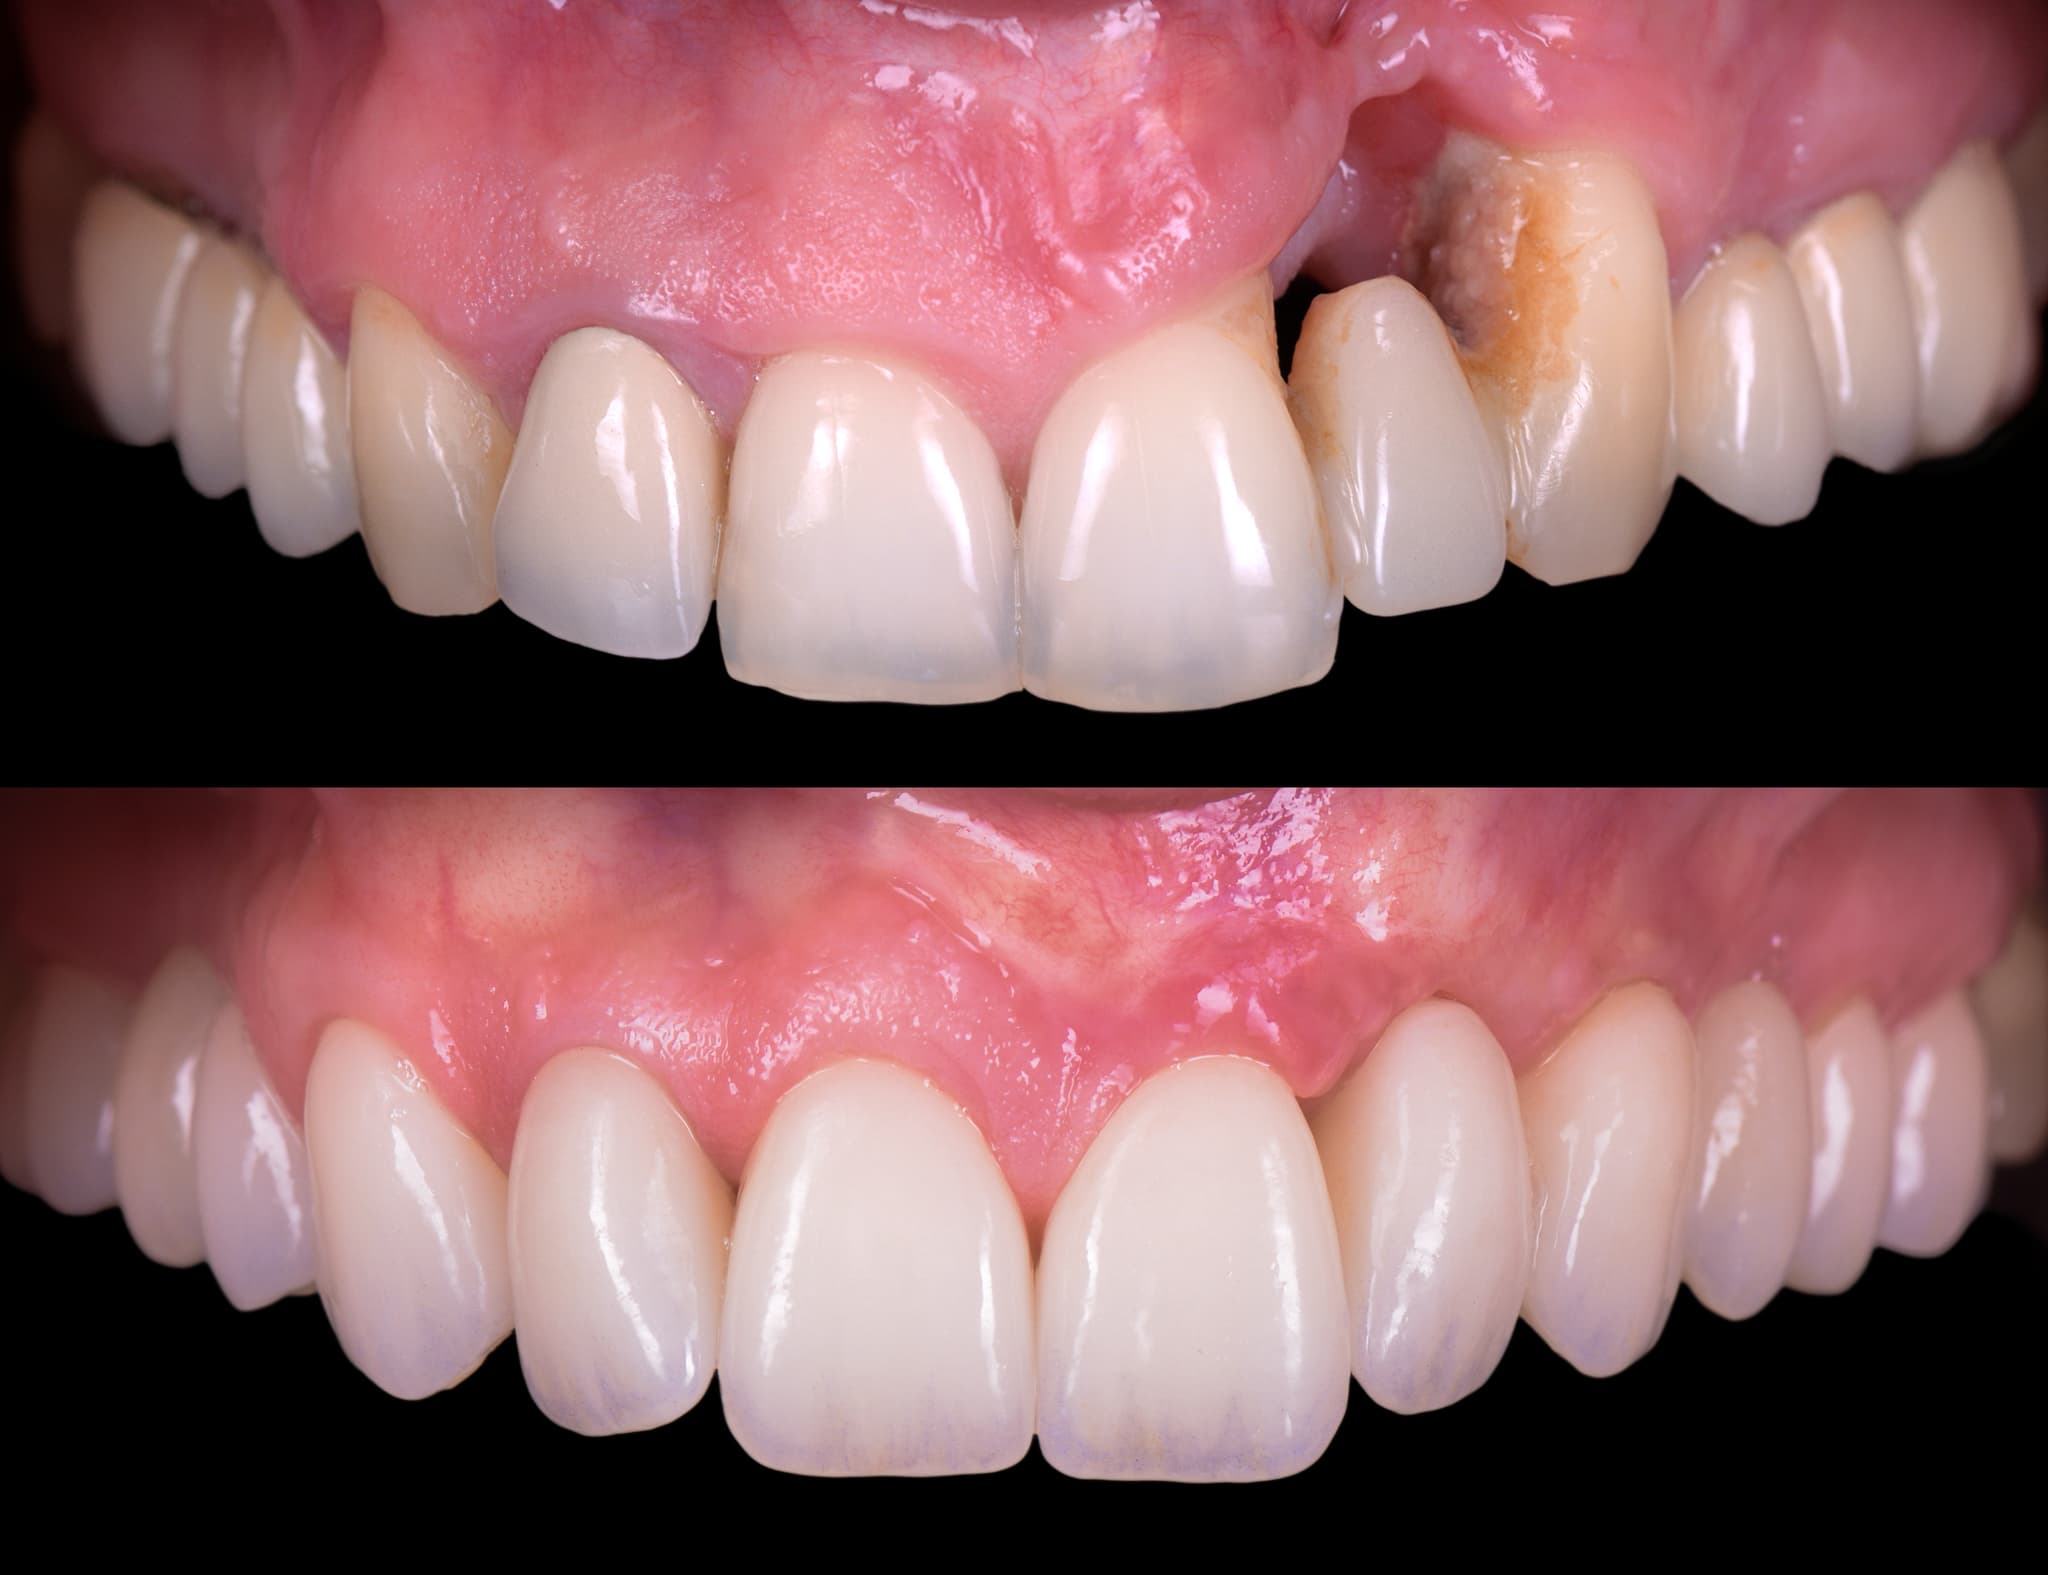

3. Regeneration and Tissue Recovery

Rebuilding where possible. Stabilizing always.

In cases with bone loss or gum recession, we assess the possibility for regeneration. Using biomaterials and guided healing principles, we rebuild support in selected areas. When future implant placement is considered, regeneration helps create a stable foundation. Our goal is not only to stop disease—but to restore architecture.